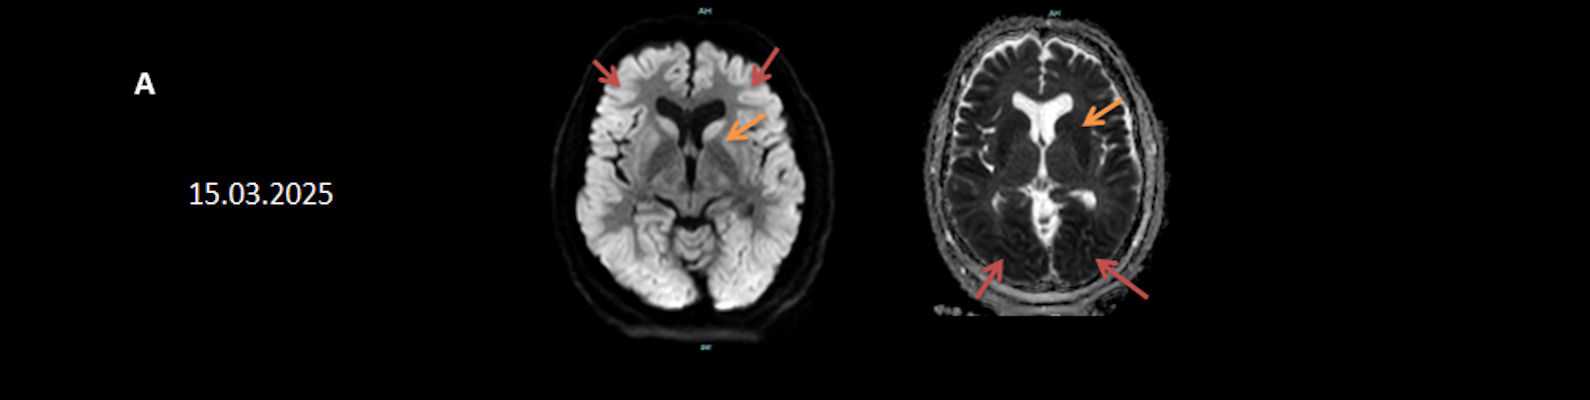

- A) Bilateral serebral kortekste (oklar) ve bazal ganglionlarda (oklar) yaygın DAG hiperintens, ADC hipointens difüzyon kısıtlamaları görülüyor.

- B) 9 gün sonraki difüzyon MR incelemede kortikal ve bazal ganglionlardaki difüzyon kısıtlamalarının gerilediği, bilateral serebral beyaz cevherde (oklar) ve internal kapsül arka bacağı- kortikospinal trakt boyunca (oklar) yaygın DAG hiperintens, ADC hipointens difüzyon kısıtlamalarının geliştiği izleniyor.